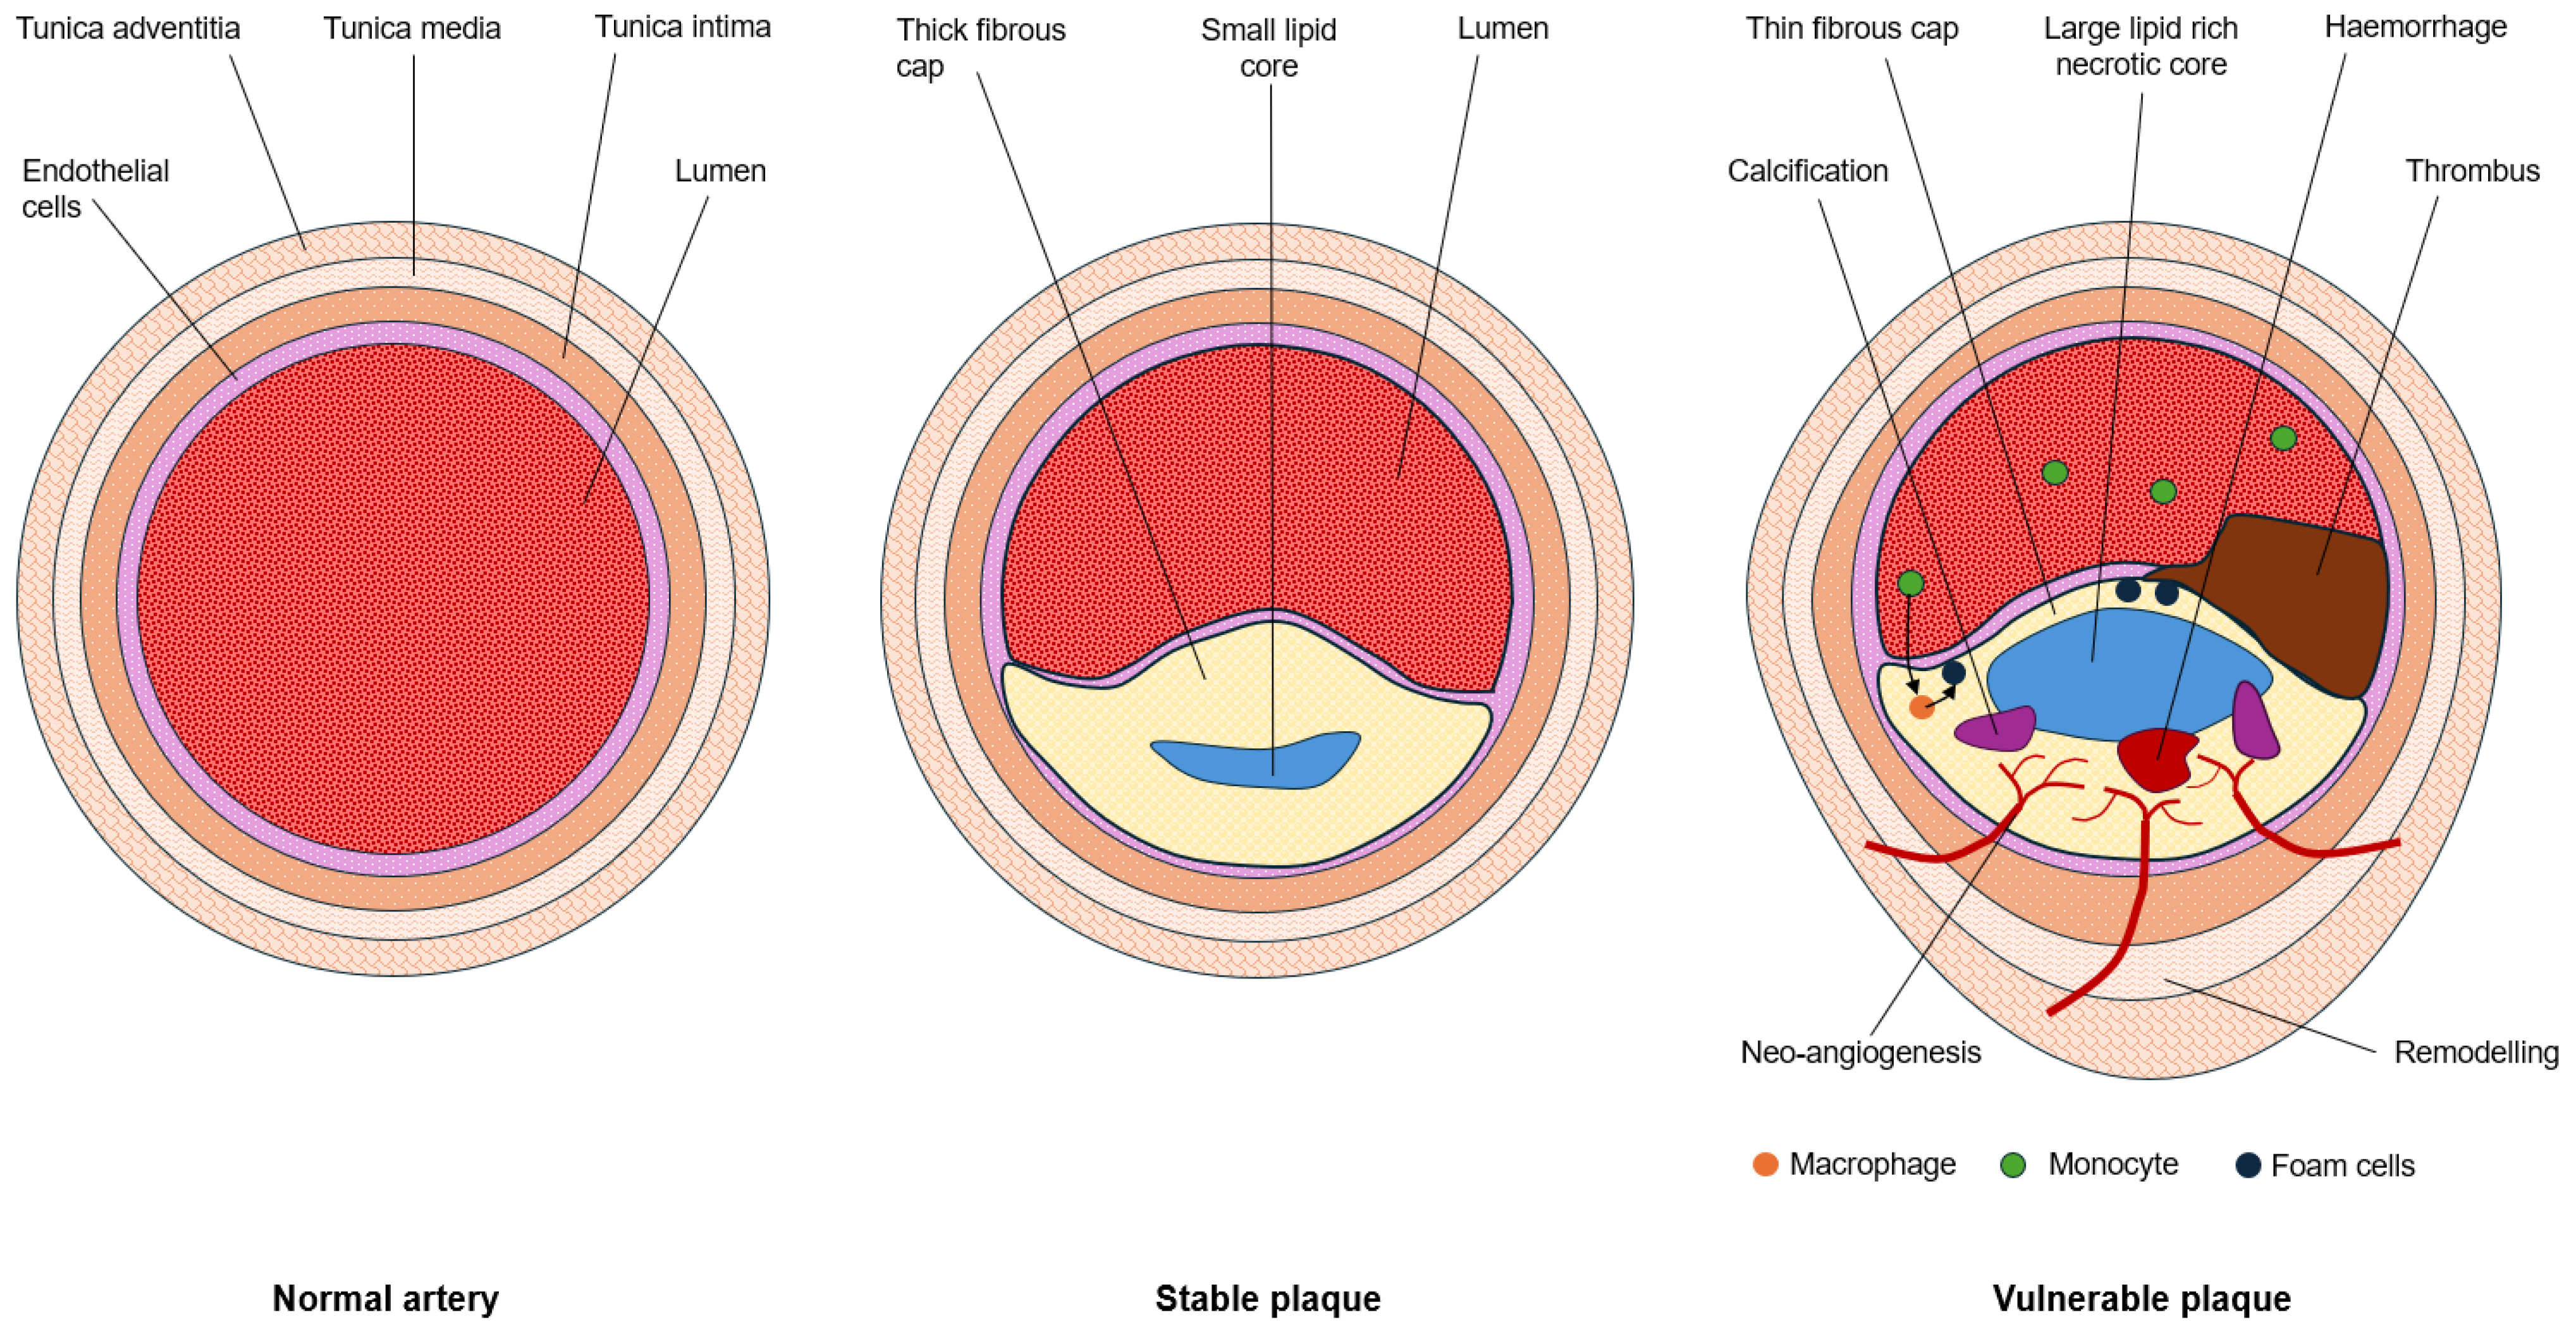

1.1. Hallmarks of Plaque Vulnerability

1.2. Imaging Plaque Morphology

1.3. Molecular Imaging of the Hallmarks of Plaque Vulnerability